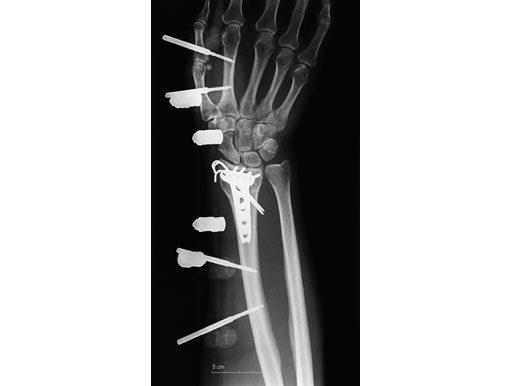

54-year-old female with 23-C3 fracture after fall

External fixator due to severe soft-tissue trauma. Palmar plate 1 week later. .